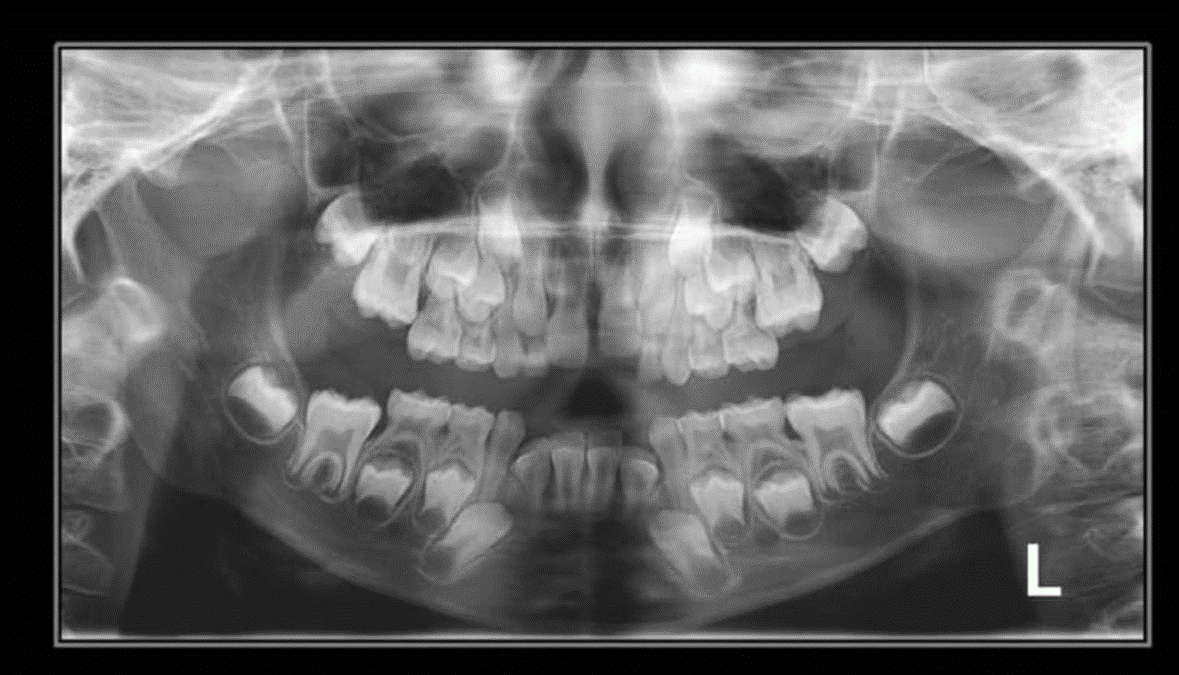

3. How old is the patient with the following X ray?